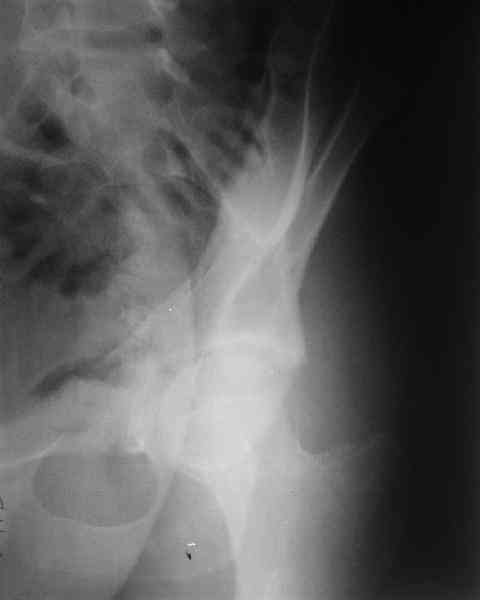

Мужчина 33 лет получил травму в шахте (придавило вагонеткой) 6 недель назад. Изолированное повреждение вертлужной впадины.

В местной больнице отлежал несколько недель на вытяжении. После выписки амбулатрный травматолог направил в институт. На сегодня, похоже, уже имеется неправиильное сращение. См. картинки.

Вопрос - что делать сейчас? Оставить как есть или идти на открытое восстановление? Если последнее, то какой доступ, репозиционные манипуляции и фиксацию тут можно посоветовать?Заранее спасибо.

Dear all,A male 23 y.o. injured 6 weeks ago - mine trauma, impacted by a carriage. Isolated injury of the acetabulum. At the initial hosptial was on bed traction some weeks. After discharge visited anotheк orthopaedic surgeon who referred him to our unit. To date looks like a malunion. Images attached. The question is about what to do now - either leave it as is or perform open reduction? If the latter what approach, reduction manoeuvres and fixation would you advice? Thx in advance!

What is your indication for surgical management? What kind of fracture do you think it is? It looks like a transverse type although it has been a couple of years since I looked at an acetabular fracture.

My concern would be that the risk of leaving it malreduced is very high. It appears to be primarily a gap rather than a step in the articular surface. Do you have any CT views that show an articular step?

The last two images from the 3-D CT scan certainly makes the fracture look worse than the plan radiographs.